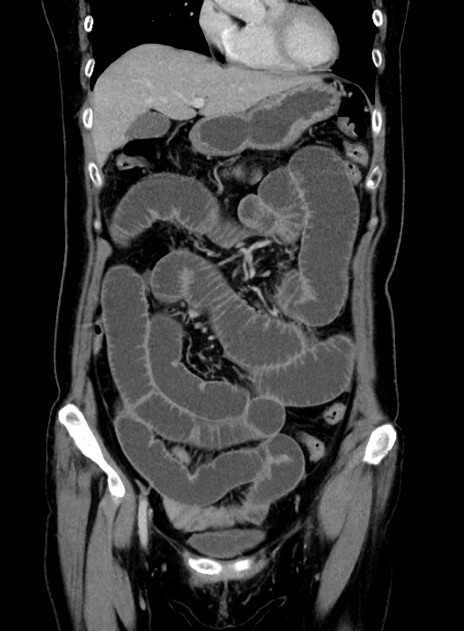

症例9(冠状断像)

【症例】 60歳代女性

【主訴】むかつき、みぞおちの痛み

【現病歴】3日前よりむかつきがあり、食事がとれない。

【既往歴】糖尿病

【身体所見】発熱なし、心窩部圧痛軽度あるも、腹膜刺激症状なし。

【データ】WBC 7400、CRP 1.92